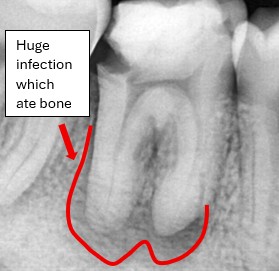

Real Patient Results – Before and After Results of Root Canal Treatment

Discover real root canal treatment results performed by our experienced dental team at Rakyat Dental. These genuine clinical X-rays highlight before-and-after transformations where patients recovered from severe infections and bone loss through advanced endodontic procedures. Each case demonstrates the precision, care, and success of our root canal treatments in preserving natural teeth.